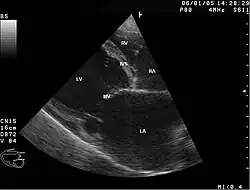

Abnormal heart sounds, murmurs, ECG abnormalities, and enlarged heart on chest x-ray may lead to the diagnosis. Echocardiogram abnormalities and cardiac catheterization or angiogram to rule out coronary artery blockages, along with a history of alcohol abuse can confirm the diagnosis.[4] It's important to note that part of diagnosing Chronic ACM is noting the absence of coronary artery disease.[7] It's also worth noting that the diagnosis of ACM is largely a diagnosis of exclusion.

In addition to the patient's medical history and physical exam, the diagnosis of alcoholic cardiomyopathy is often confirmed with various diagnostic tests.[8] One of the most common tests is an echocardiogram, which uses ultrasound waves to create images of the heart and can detect abnormalities in the heart's structure and function.[8] Other tests may include an electrocardiogram (ECG) to measure the heart's electrical activity, and blood tests to check for elevated levels of certain enzymes that may indicate heart damage.[8] If the diagnosis is confirmed, treatment typically involves stopping alcohol consumption and managing heart failure symptoms through medications, lifestyle changes, and in severe cases, heart transplantation.[8]

Labeled chambers